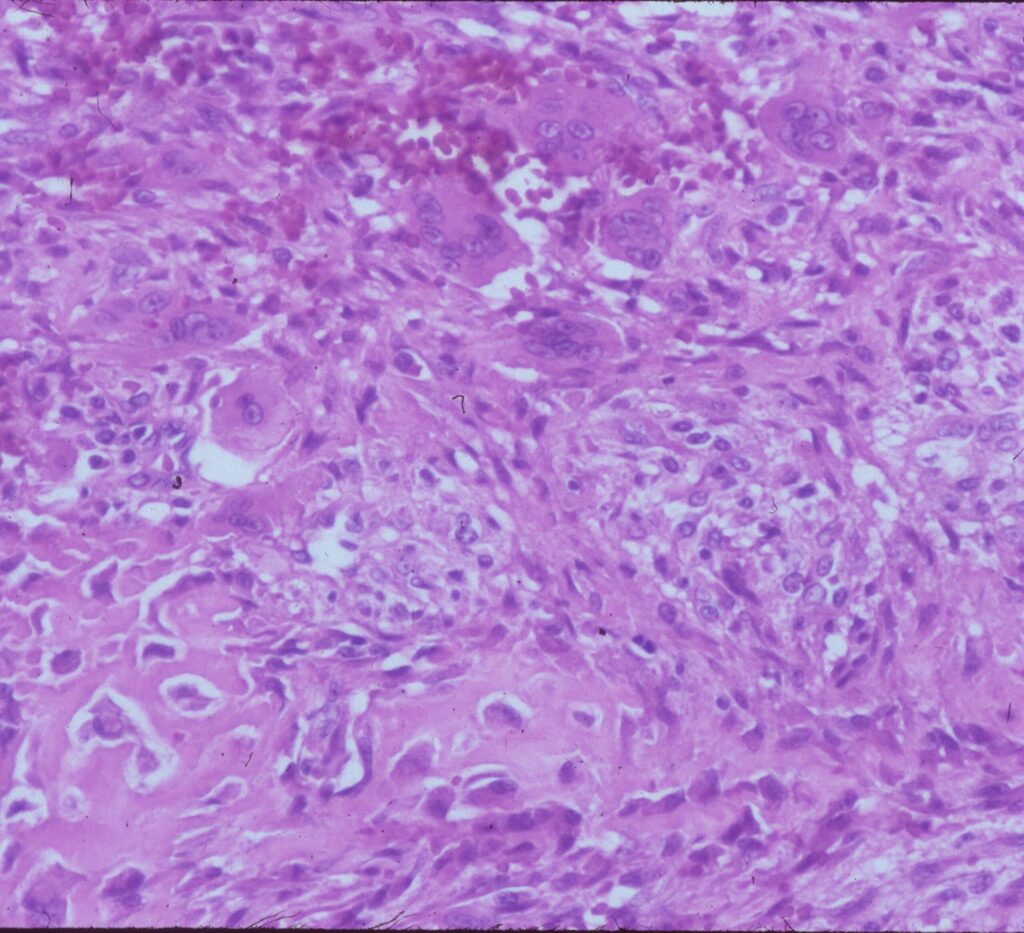

Microscopic Pathology

- Hemorrhagic tissue with large cavitary spaces divided by septum of spindle fibroblastic cells, inflammatory cells and few giant cells.

- Osteoid formation could be noted (reactive and benign in nature)

Fig 3 a,b,c. Microscopic pathology of an Aneurysmal Bone Cyst (ABC):

Figure 3a: There is a large blood filled cystic cavity surrounded by a fibrous septae that includes benign appearing spindle cells, fibrous extracellular matrix and scattered giant cells. There are areas of reactive bone formation. The fibroblastic cells are bland appearing. There are no abnormal mitotic figures.

Fig 3b: Intermediate power of a septum of an ABC: There is no epithelial lining around the wall of the cavity filled with blood. There are spindle cells and scattered giant cells.

Fig 3c: High power view of an ABC: Demonstrates reactive bone formation within the wall of the cystic cavities. This is reactive bone and different from the lace like immature bone layed down by an osteosarcoma